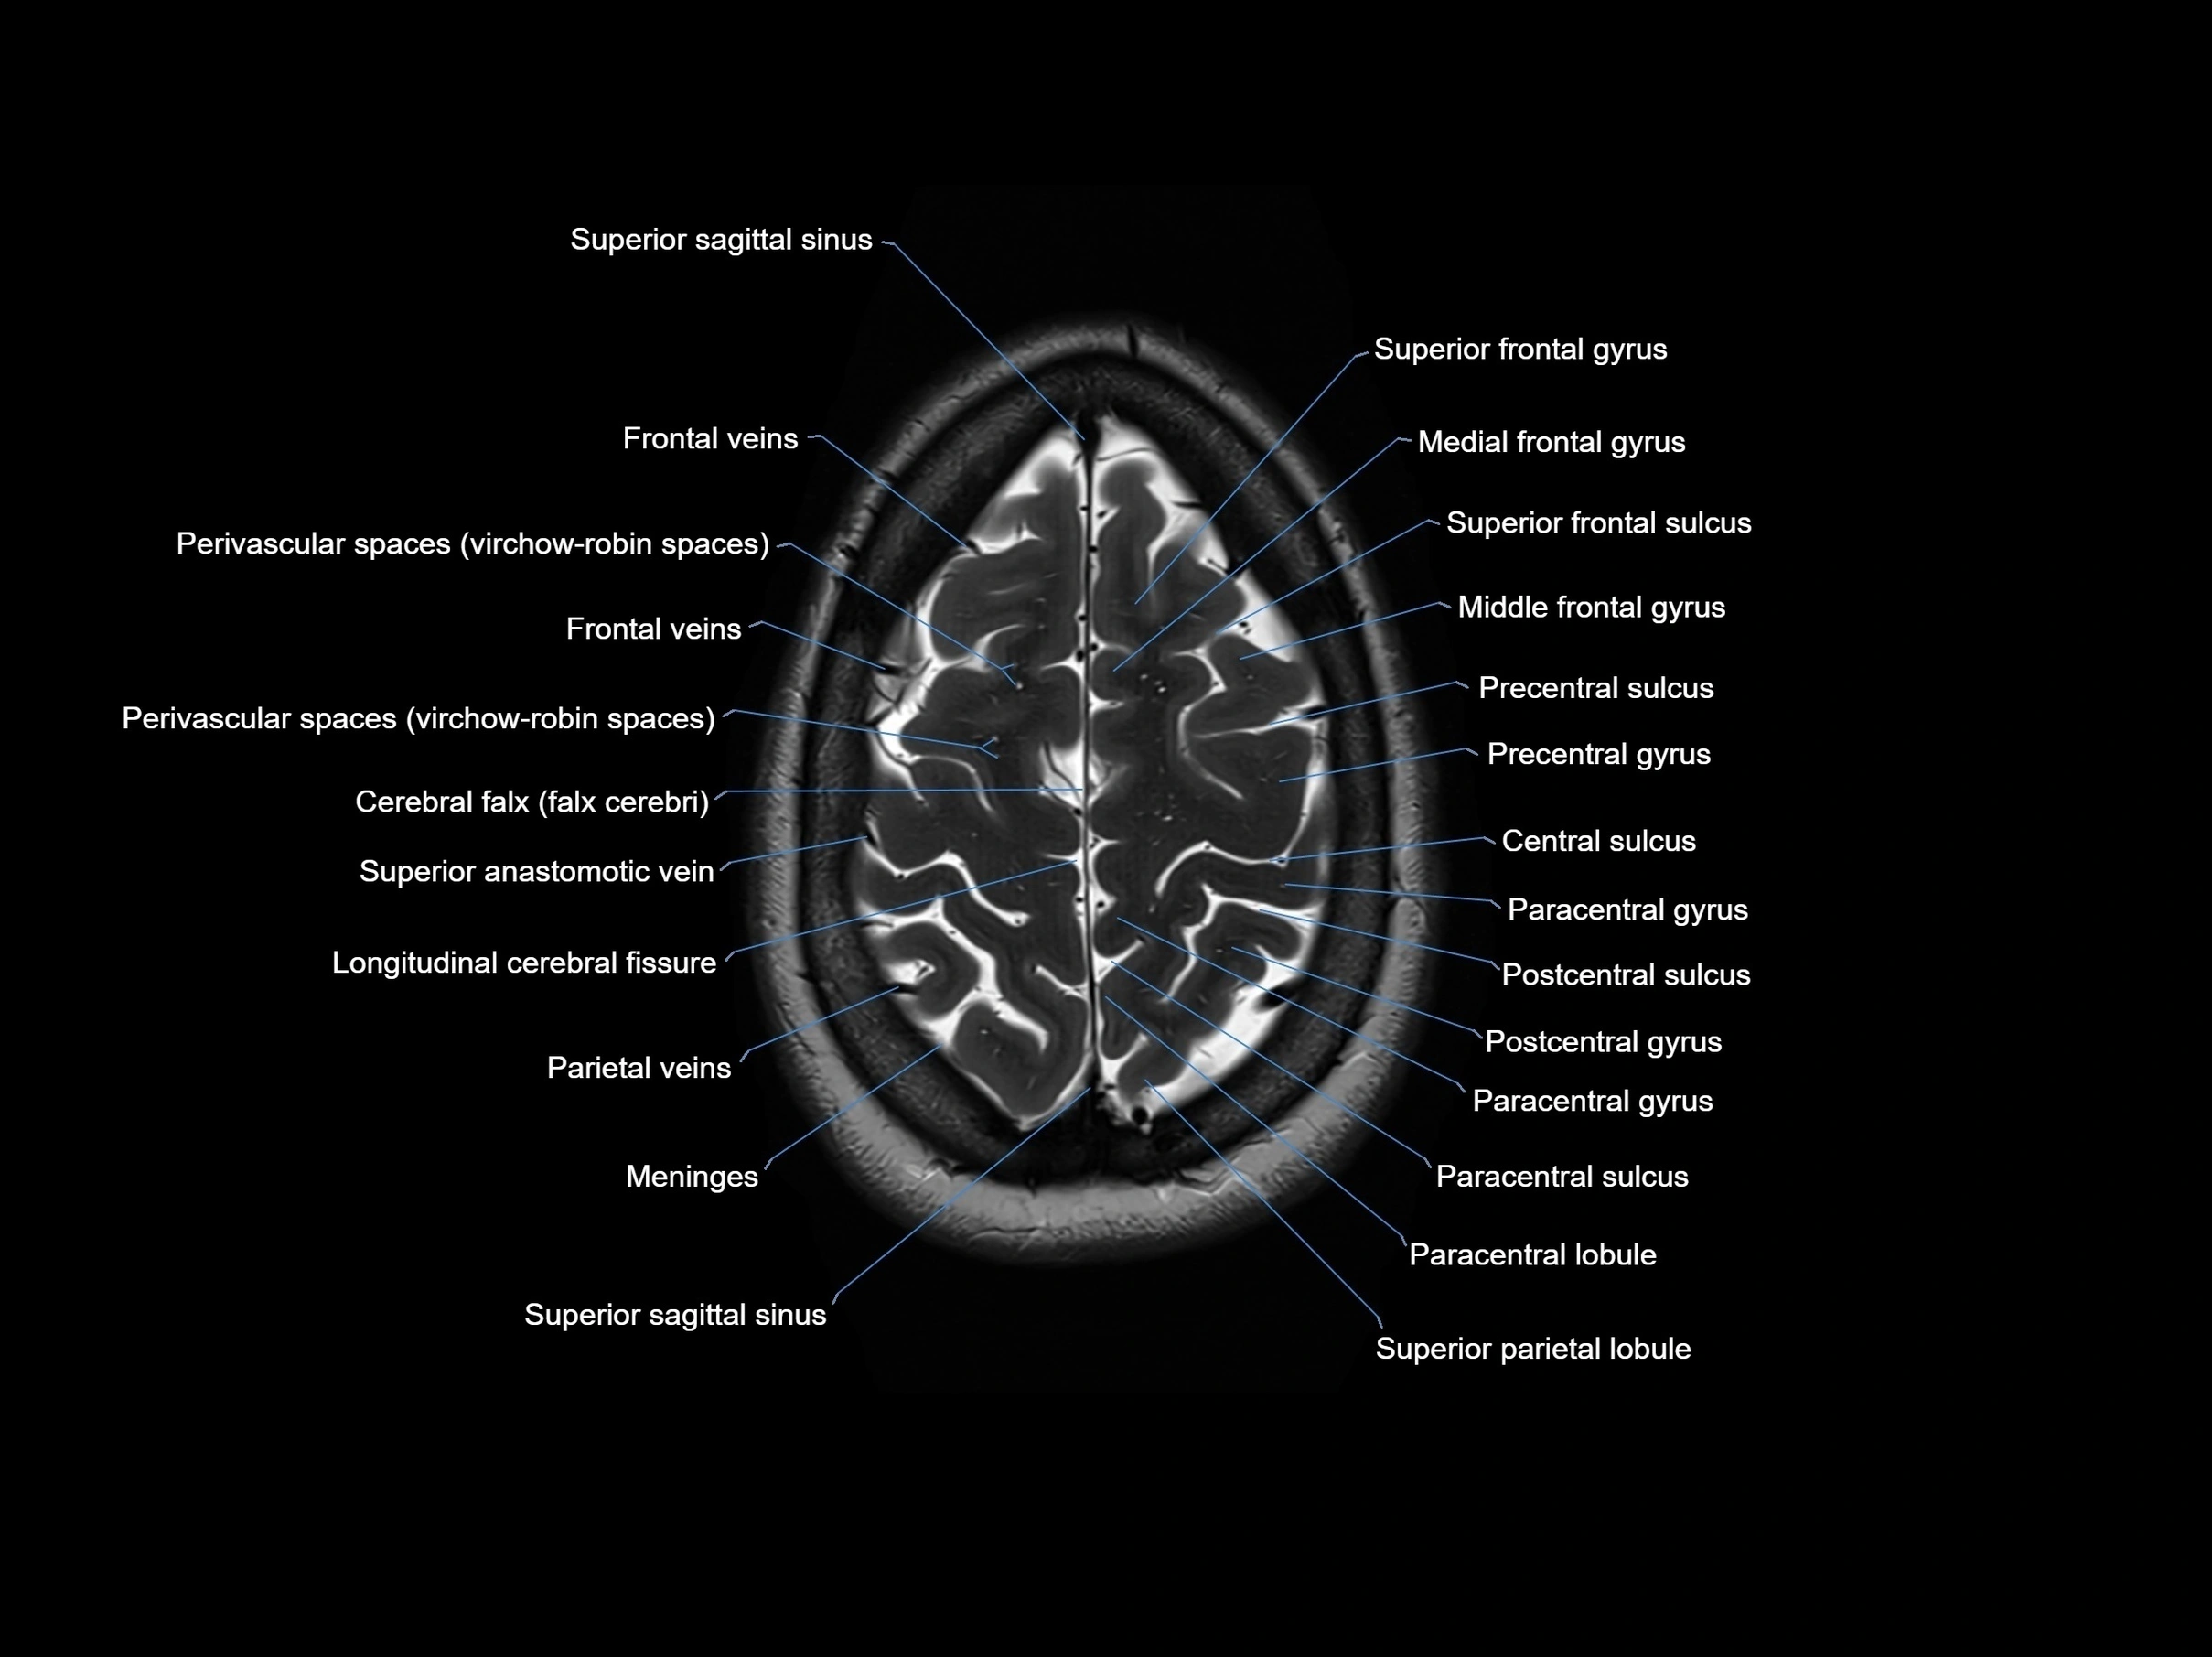

- Cerebral falx

- Longitudinal cerebral fissure

- Meninges

- Paracentral gyrus

- Paracentral lobule

- Paracentral sulcus

- Parietal veins

- Postcentral gyrus

- Postcentral sulcus

- Precentral gyrus

- Precentral sulcus

- Sagittal suture

- Superior frontal gyrus

- Superior frontal sulcus

- Superior occipital gyrus

- Superior parietal lobule

- Superior sagittal sinus